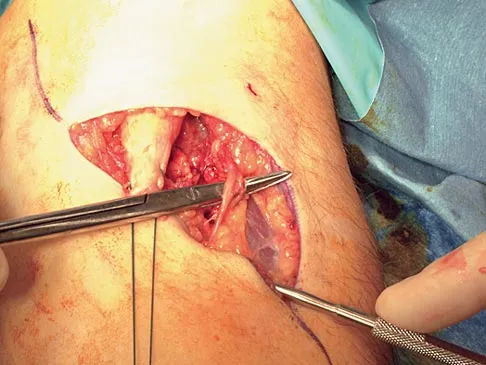

Figures 11a and 11b show the T2-weighted MRI scans of the lumbar spine of a 53-year-old woman who has low back and right lower extremity pain. What structure is the arrow pointing to in Figure 11a?

Detailed Explanation